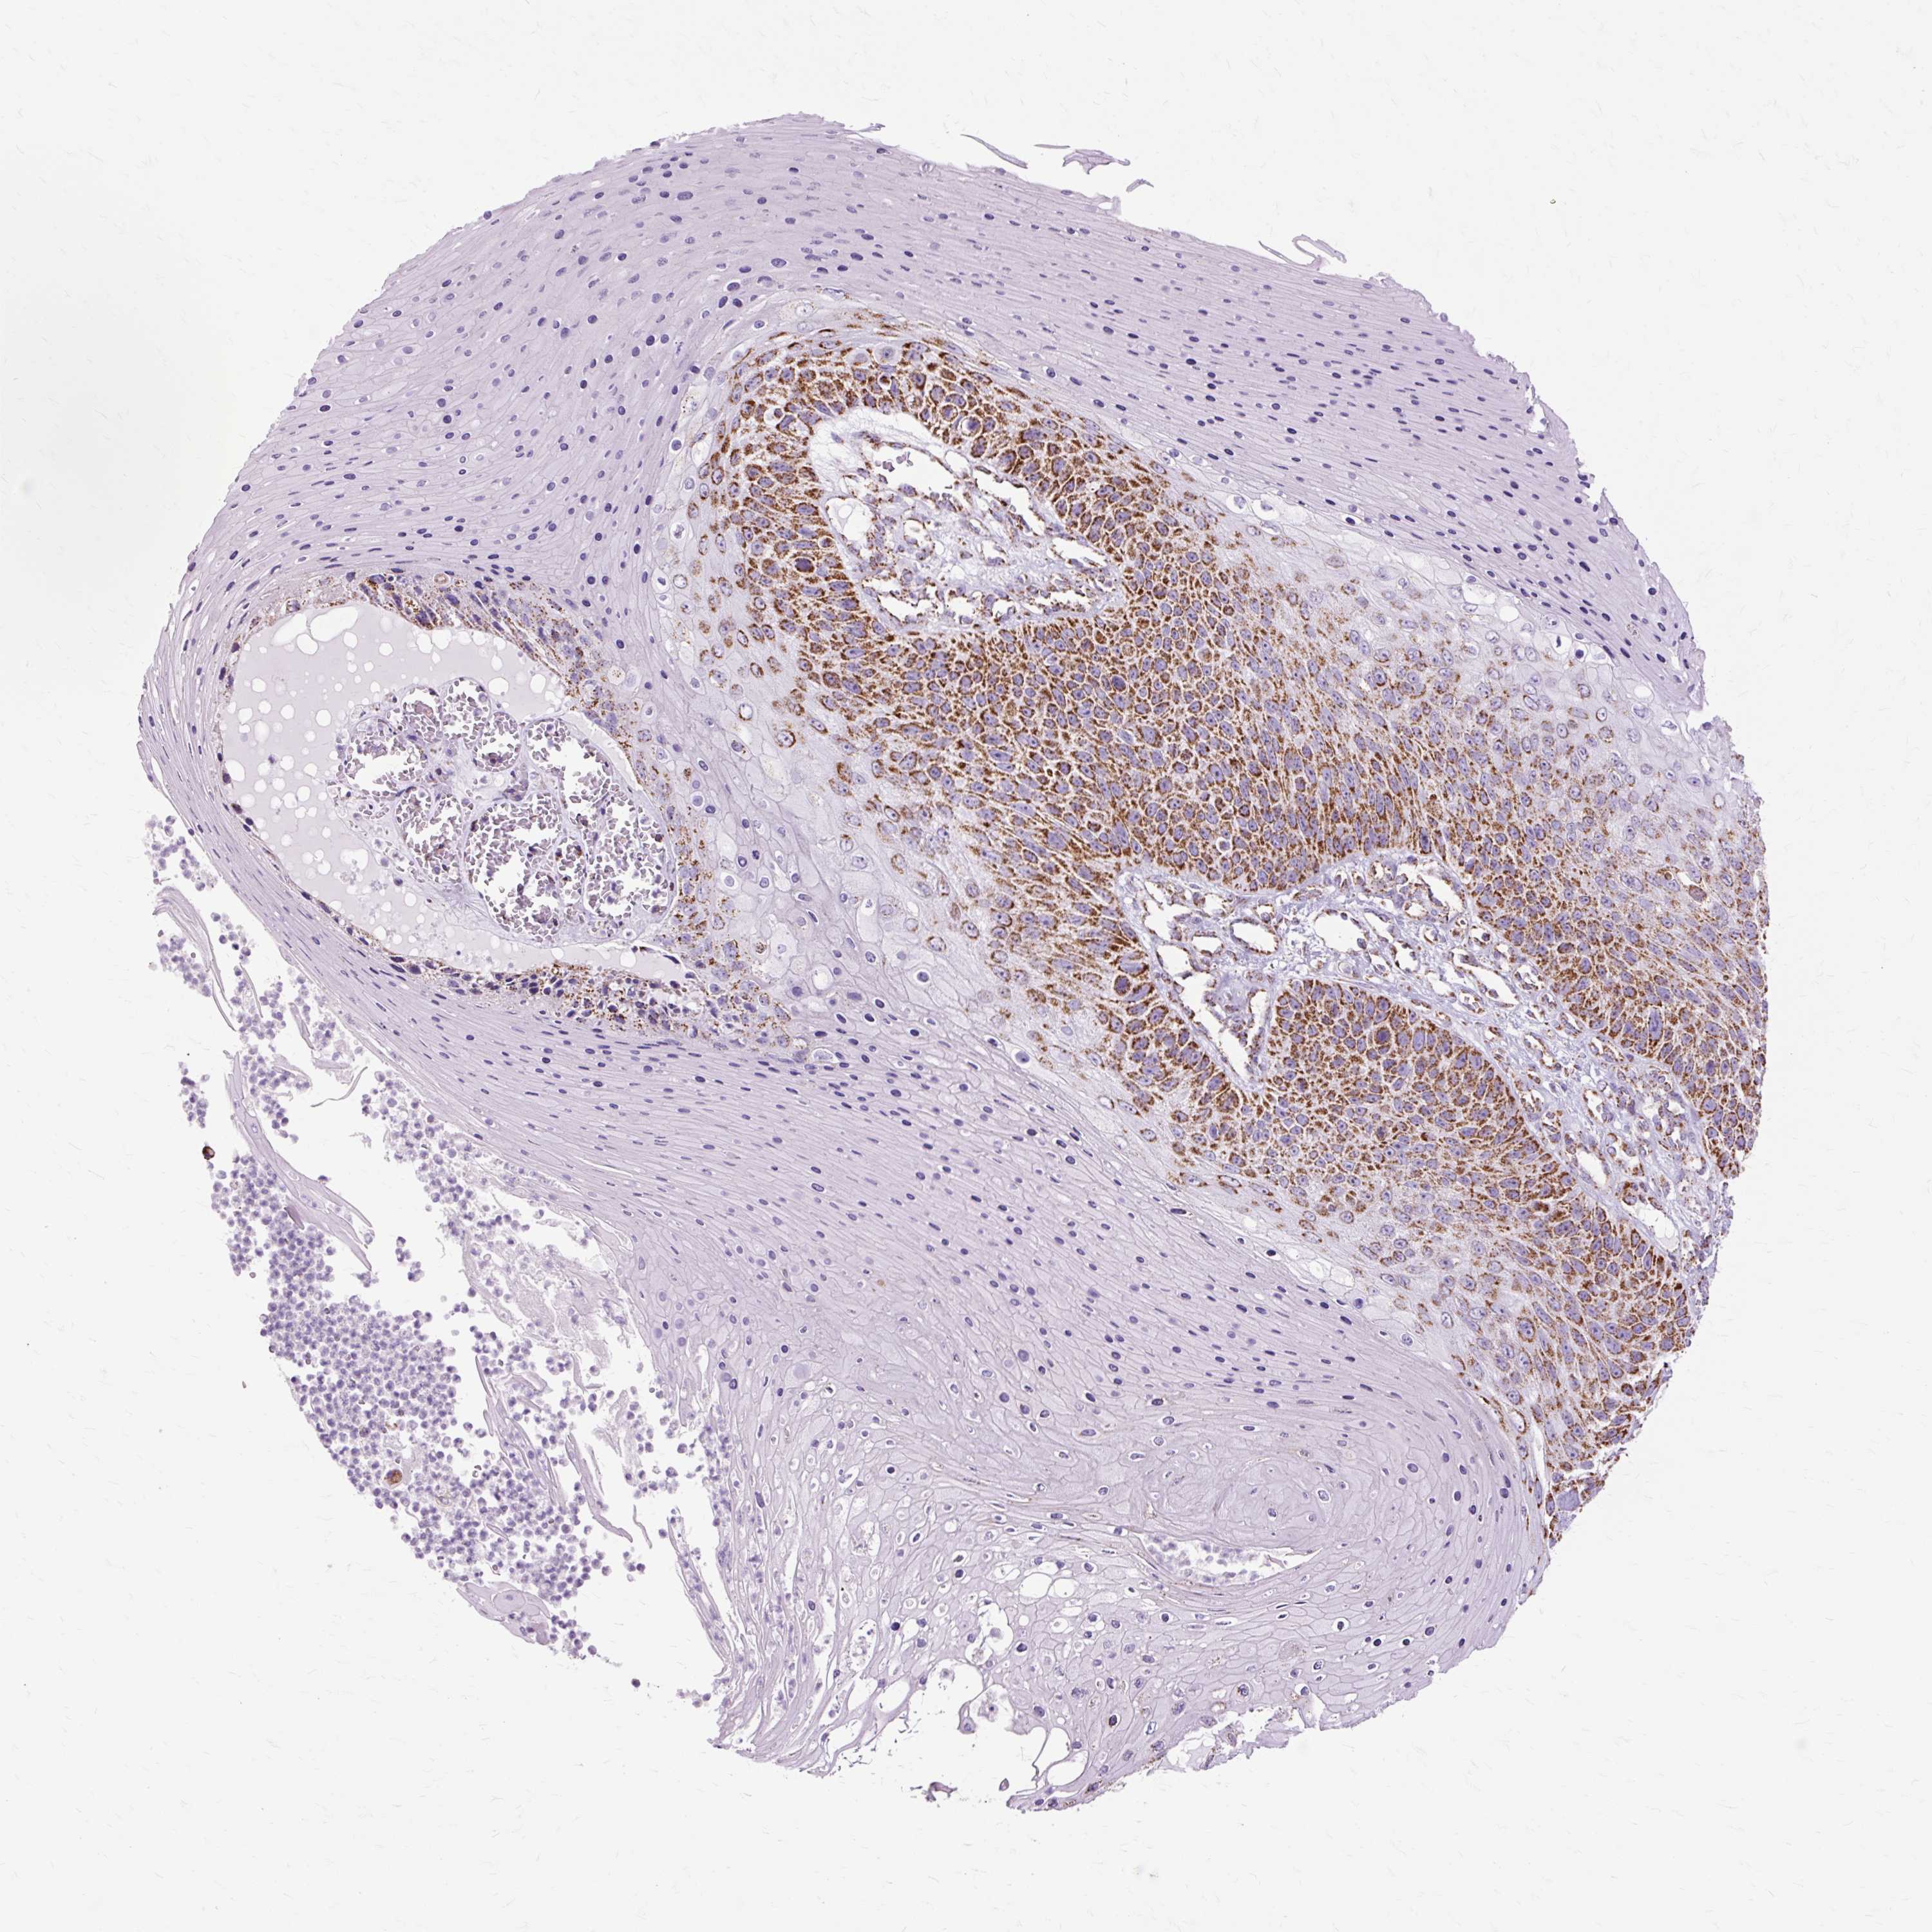

SKIN CANCER - Protein expressioni

A mouse-over function shows sample information and annotation data. Click on an image to view it in a full screen mode. Samples can be filtered based on level of antibody staining by selecting one or several of the following categories: high, medium, low and not detected. The assay and annotation is described here.

Antibody stainingi

Antibody staining in the annotated cell types in the current human tissue is reported as not detected, low, medium, or high, based on conventional immunohistochemistry profiling in selected tissues. This score is based on the combination of the staining intensity and fraction of stained cells.

Each image is clickable and will lead to virtual microscopy that enables deeper exploration of all samples and also displays staining intensity scores, fraction scores and subcellular localization as well as patient and tissue information for each sample.

Antibody CAB003782

Staining

High

Medium

Low

Not detected

Intensity

Strong

Moderate

Weak

Negative

Quantity

>75%

75%-25%

<25%

None

Location

Nuclear

Cytoplasmic/membranous

Cytoplasmic/membranous,nuclear

Squamous cell carcinoma, metastatic, NOS

Squamous cell carcinoma, NOS

Basal cell carcinoma